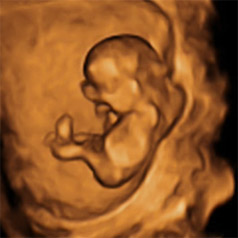

En esta semana además tiene lugar un hecho muy importante e inolvidable en la vida de la embarazada: es probable que le hagan su primera "foto", la ecografía de la semana 12.

Semana 12 de embarazo, el bebé se mueve a sus anchas

El bebé gracias a sus músculos ya es capaz de hacer muchos movimientos: gira la cabeza, encoje y estira brazos y piernas, cierra los puños… Es cierto que la futura madre aún no es capaz de sentir los movimientos del bebé, pero en la ecografía si el bebé no está dormido (suele ocurrir) quizás se puedan ver.

¿Cómo identificar el sexo de un bebé de 12 semanas?

"Habitualmente alrededor de las 12 semanas podemos diferenciar el tubérculo genital masculino y femenino. Según su disposición y orientación, a partir de ese momento podemos determinar el sexo fetal".

Dra. Raquel Mula, especialista en Alto Riesgo Obstétrico de Dexeus Mujer.

“¿Niño o niña?”, le preguntarás al médico. Y quizás pueda responderte. Los órganos sexuales externos ya se han formado, pero no siempre en la ecografía se pueden distinguir con claridad, por eso en esta primera ecografía el especialista no siempre anuncia a los futuros padres si el bebé que esperan es niño o niña.